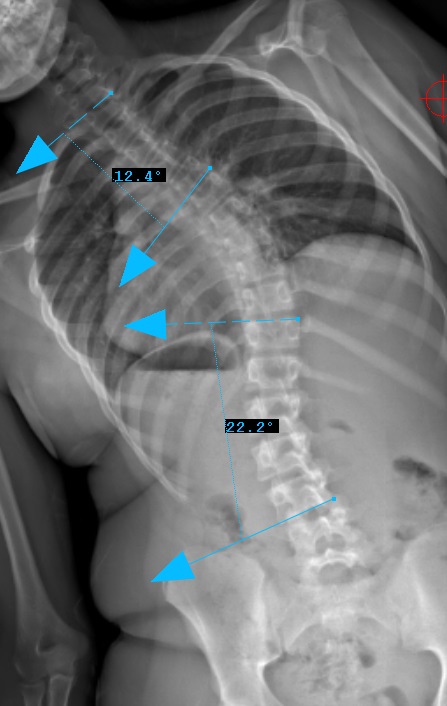

Preop: 1C- Examples

Preop LEFT Bend

Curve Type 1

Thoracic curve major, other curves non-structural (bend out to <25o)

Lumbar modifier C

CSVL does not touch apex of lumbar curve

(apex - L1/2 disc)

Therefore, Classification is Type 1C-